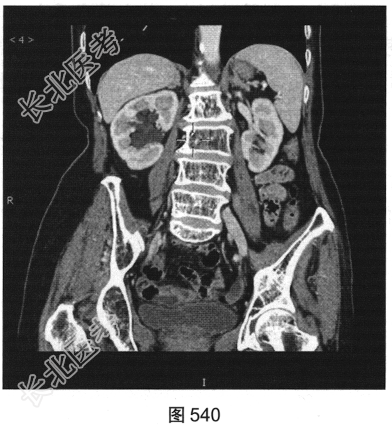

- 多项选择题3.[提示]CT平扫+增强(图538~图542)所见:双侧肾盂肾盏旁可见沿肾盂肾盏走行的多发囊样低密度灶, 未见明显强化。应考虑的鉴别诊断为( )

A、肾外肾盂旁血管病变

B、肾盂旁肿瘤性病变

C、囊性肾癌

D、肾盂旁囊肿

E、肾积水

F、肾窦内脂肪沉积症